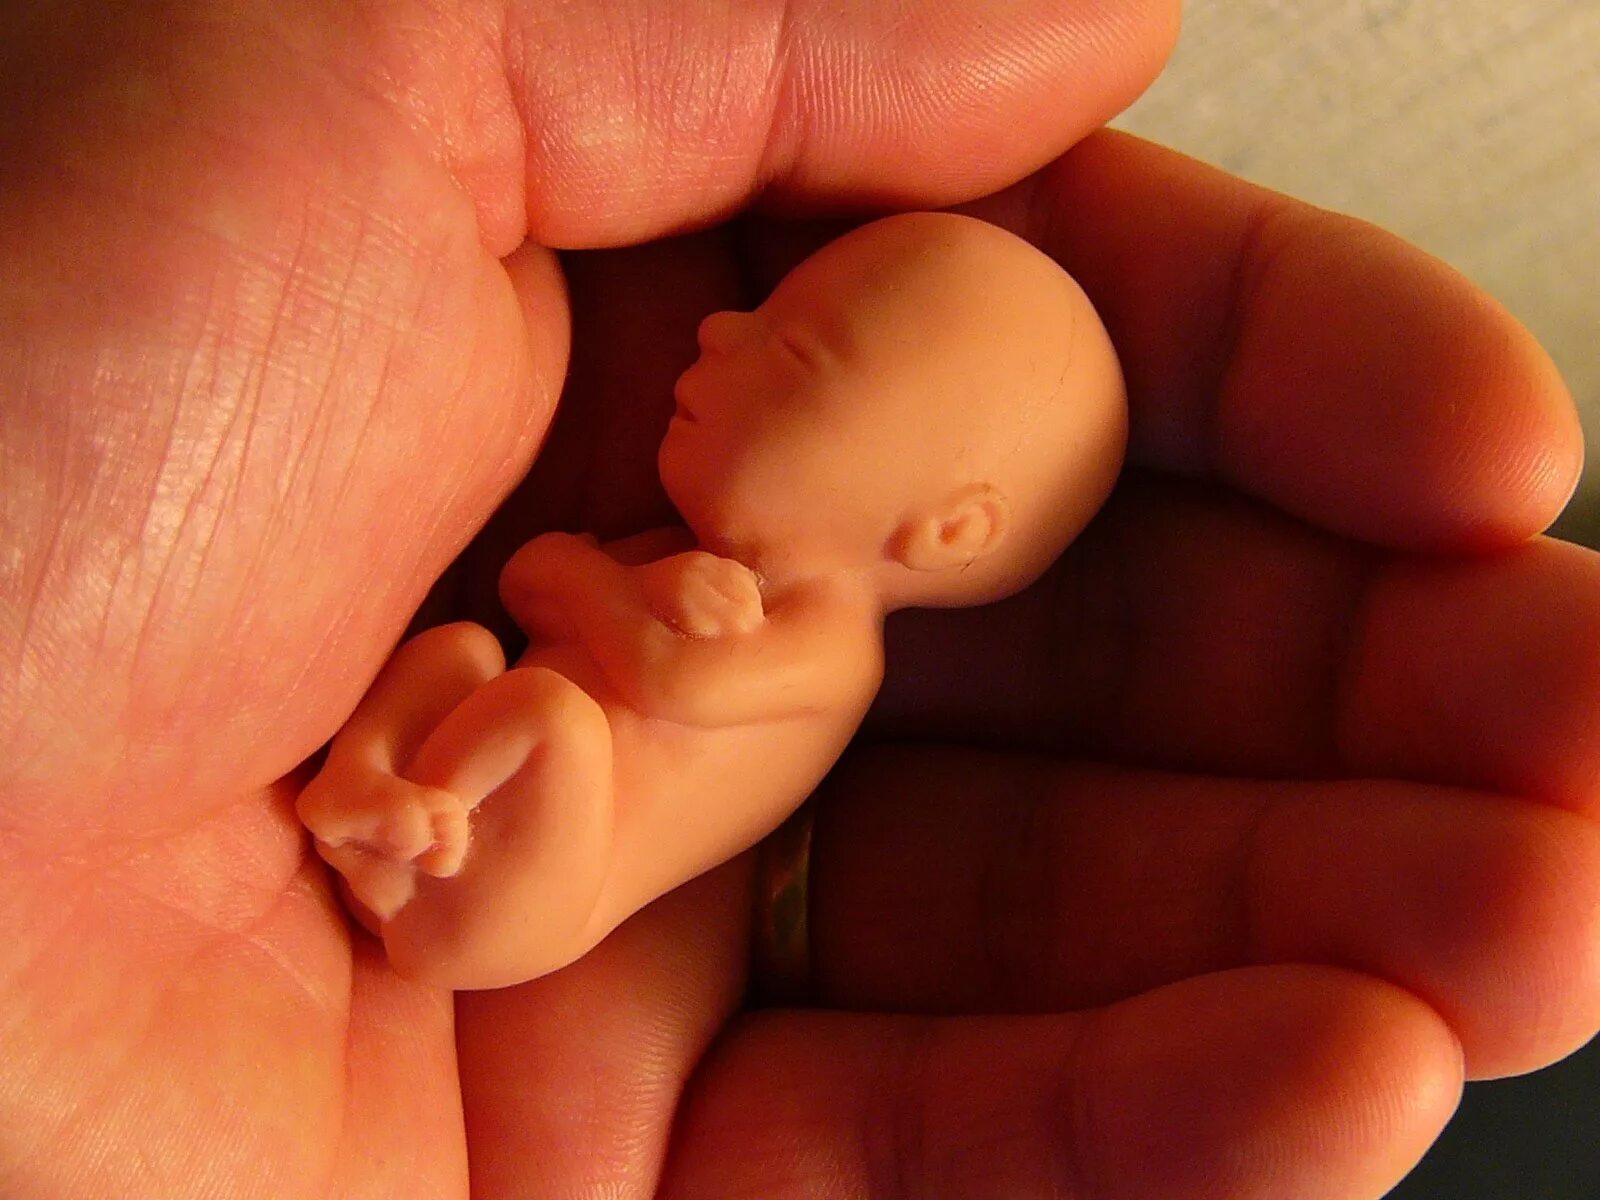

Ребенок в 13 недель